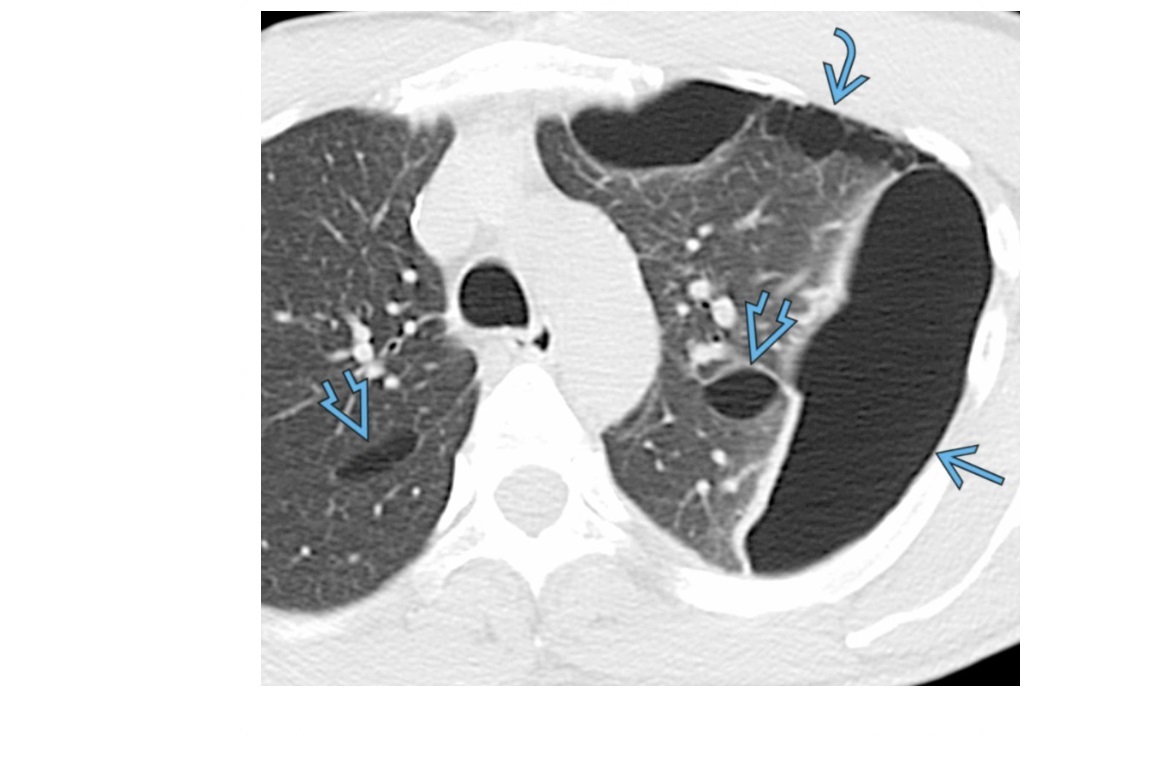

Lymphoid Interstitial Pneumonia - LIP

Basilar predominace

Thin walled cysts

GGO

Centilobualr micronodules

GGO clears with treatment

Associated with Sjogren’s

+ PCP, Hep B, EV

+ AIDs